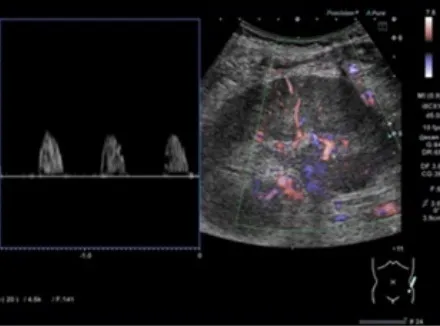

Uma causa incomum de hematúria glomerular intermitente!

Uma causa incomum de hematúria glomerular intermitente!

Hematúria pós infecção, caso clínicos para auxiliar no entendimento de causas glomerulares comuns e raras...